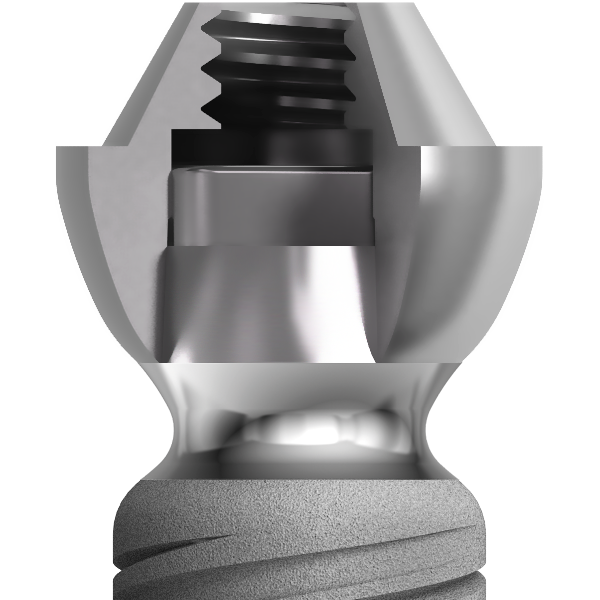

Le twinKon® présente un épaulement arrondi au niveau duquel se trouve la limite lisse-rugueuse de l’implant. Cet épaulement est surmonté d’un col concave lisse, en contact avec le tissu conjonctif.

L’objectif de ce col concave est de recréer un joint muqueux de première intention qui jouera le rôle de barrière naturelle. Toutes les manipulations prothétiques à suivre sont décalées au-dessus de cette limite, réduisant ainsi le risque de contamination iatrogène au profit de la préservation du capital osseux résiduel.